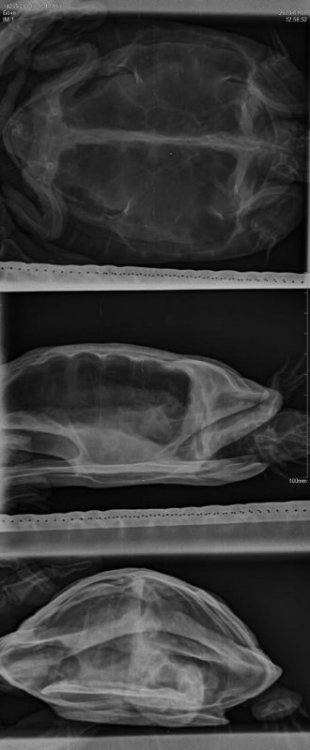

Gintaras Ваше имя: Gintaras Локация: Нижневартовск Опубликовано: 8 января 2020 Автор Опубликовано: 8 января 2020 Рентген сделали, воспаления нет. Подскажите,что делать, чем лечить??

Podolnyi Ваше имя: Подольный Константин Локация: Украина, Днепр Опубликовано: 9 января 2020 Опубликовано: 9 января 2020 У черепахи сильный метеоризм (вздутие) жкт с перезаполненным кишечником массами. Вам минимально стоит начать с элеовита, кальция глюконата/борглюконата, вибротерапия. когда кал был последний раз? грунт не ест?